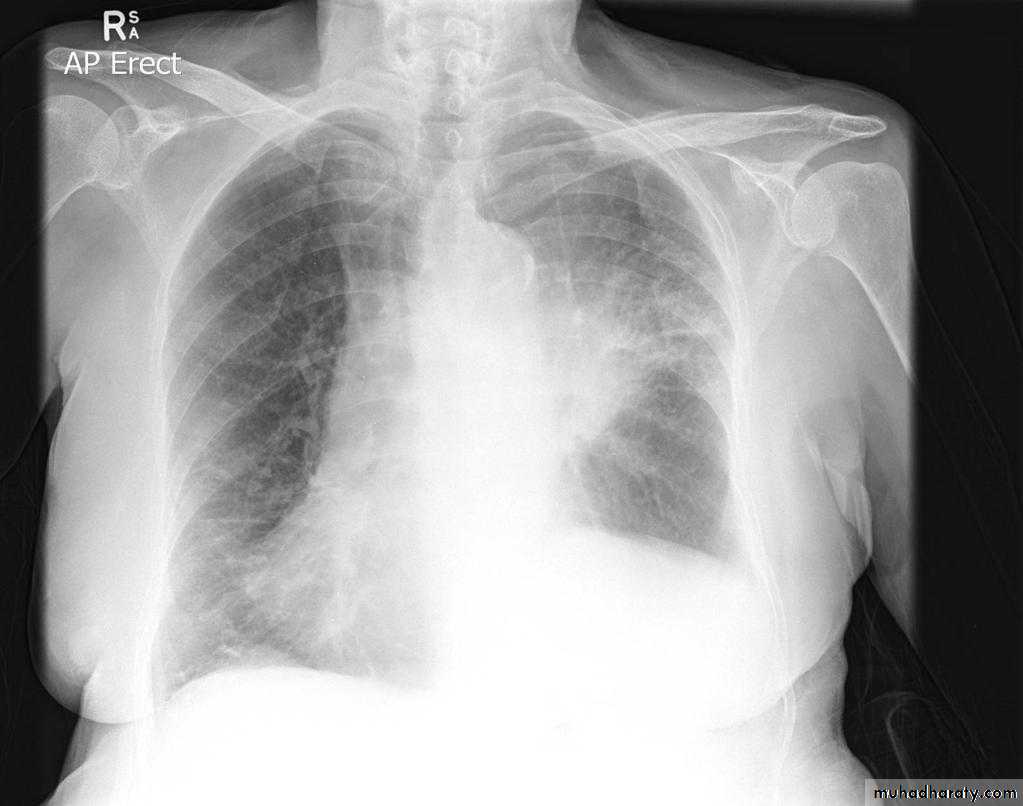

Pleural effusion

50.pleural effusion

51.pleural effusion .